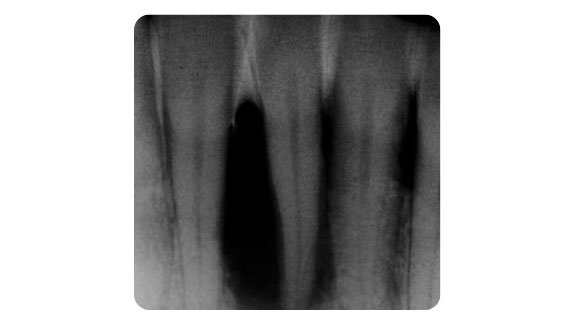

Tratament parodontal cu piesa de mână Paro: Terapie inițială

Obiectivele esențiale ale terapiei inițiale sunt îndepărtarea temeinică a biofilmului, secțiunilor mineralizate ale biofilmului sub formă de tartru, precum și netezirea suprafețelor rădăcinii până la baza buzunarului. Componentele mineralizate nu declanșează inflamațiile parodontale, însă sunt un teren fertil ideal pentru dezvoltarea bacteriilor patogene parodontale.

Cu instrumentele Paro perfect compatibile din oțel chirurgical de înaltă calitate, această terapie poate fi efectuată în mod eficient și cu succes în clinici. Cele mai mici particule de hidroxilapatită și fosfat de calciu în Vector Fluid polish contribuie la curățare, în combinație cu sistemul Vector . Suspensia reduce hipersensibilitatea în timpul tratamentului. Buzunarul este întotdeauna clătit intens. Prin efectele hidrodinamice, numărul de bacterii este redus drastic.

Molari

Chiar și după curățarea temeinică a suprafaței rădăcinii, în câteva zile în buzunarele parodontale se formează bacterii. Din acest motiv, după terapia inițială trebuie efectuate în mod regulat terapii de întreținere sau terapii împotriva parodontitei (UPT) suplimentare, pentru a preveni reinfecția buzunarelor. Frecvența sesiunilor Recall trebuie stabilite individual pentru fiecare pacient în parte.